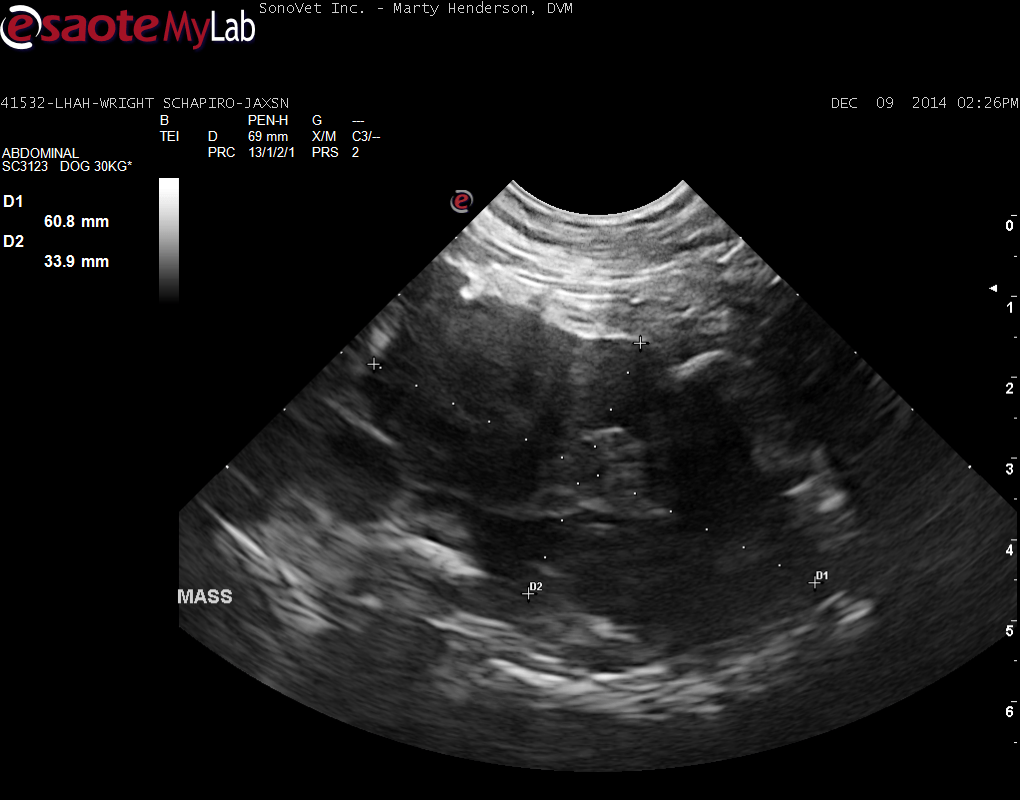

A 7-year-old MN Shepherd Mix was presented for evaluation of tenesmus with no other obvious signs. On rectal palpation a mass on the ventral aspect of the lumbar spine that starts approximately 0.5 cm into the pelvic canal and extends cranial for about an inch